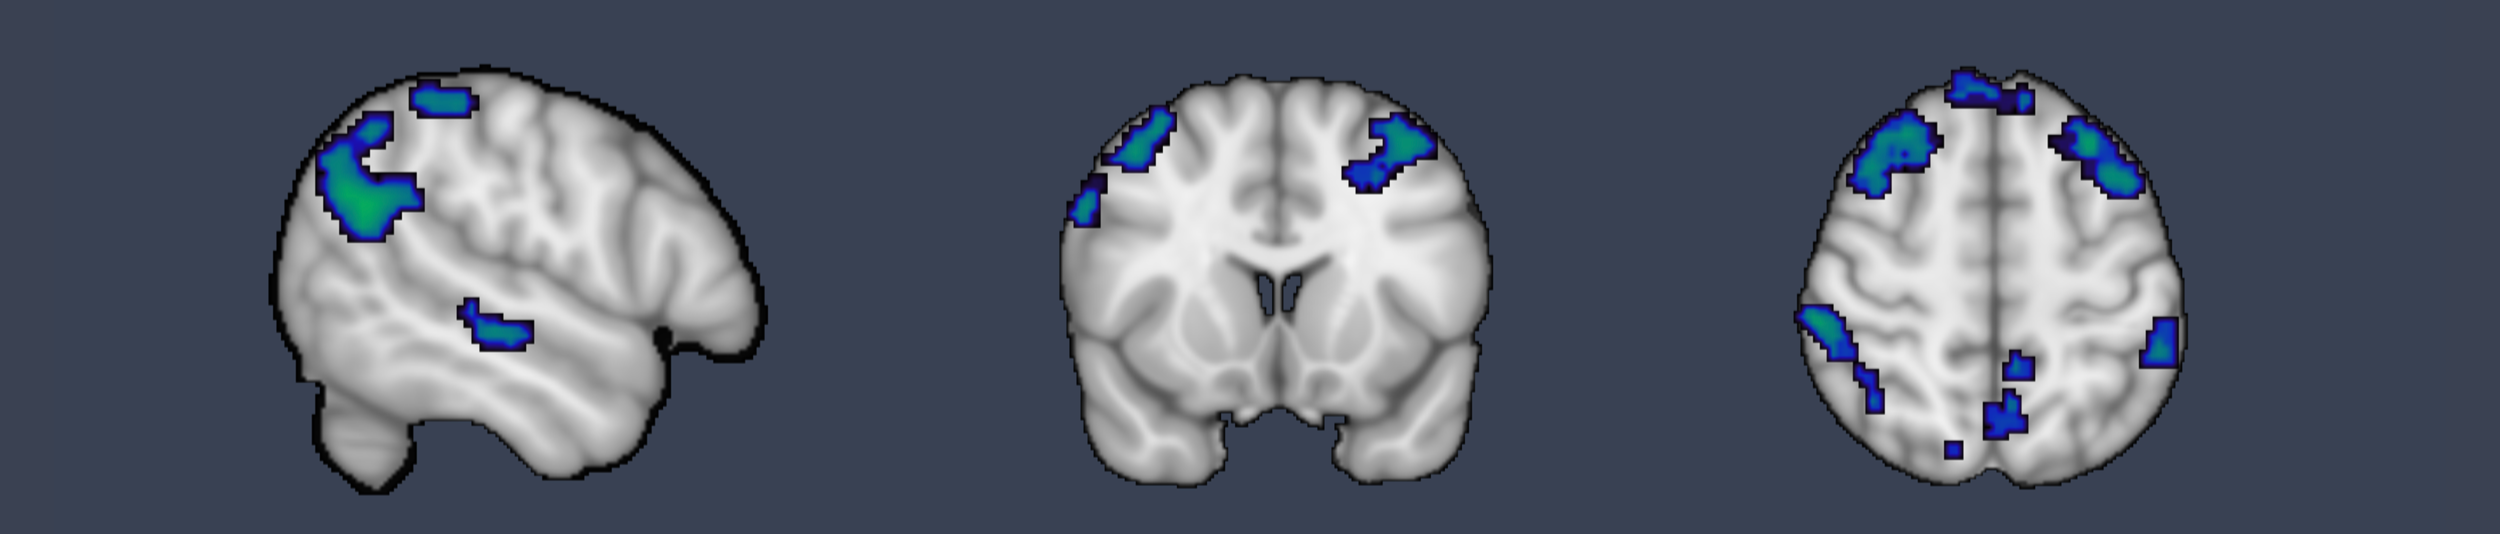

Hacia una comprensión mecanística de la reducción del estrés basado en mindfulness (MBSR) utilizando un enfoque de neuro-imágenes - RCT: Efectos en la regulación del propio estrés en situaciones sociales y no sociales

No se sabe del todo si los efectos de la regulación de las emociones (RE) de la MBSR se generalizan a los entornos sociales. En un ensayo controlado y aleatorizado investigamos los efectos del MBSR utilizando una tarea de fMRI de regulación de la emoción social y propia. Conductualmente, corroboramos los efectos en la regulación de la emoción cuando se regula a uno mismo pero no cuando se regula a los demás. A nivel cerebral, la auto-regulación se acompañó de cambios en las cortezas parietal e insular, mientras que la regulación de la emoción social se acompañó de cambios en las regiones precuneus y parietal. La revalorización cognitiva y la aceptación son dos mecanismos de regulación de la emoción del MBSR en la auto-regulación, pero no en la regulación social.